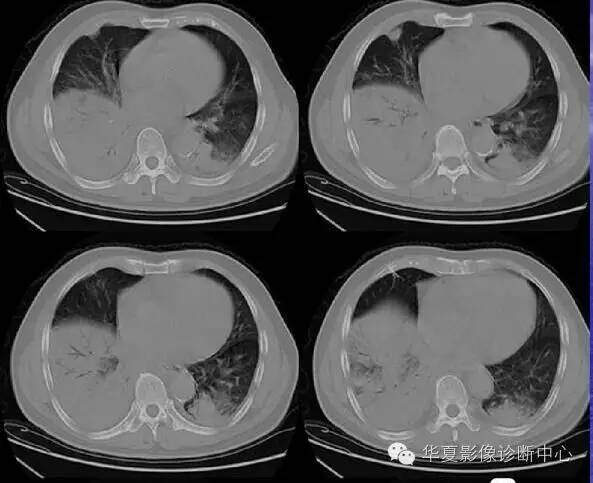

间质性肺炎

以肺间质为主的炎症,可由细菌、支原体、衣原体、病毒或肺孢子菌等引起。累及支气管壁以及支气管周围,有肺泡壁增生及间质水肿,因病变仅在肺间质,故呼吸道症状较轻,异常体征较少。X线通常表现为一侧或双侧肺下部的不规则条索状阴影,从肺门向外伸展,可呈网状,其间可有小片肺不张阴影。